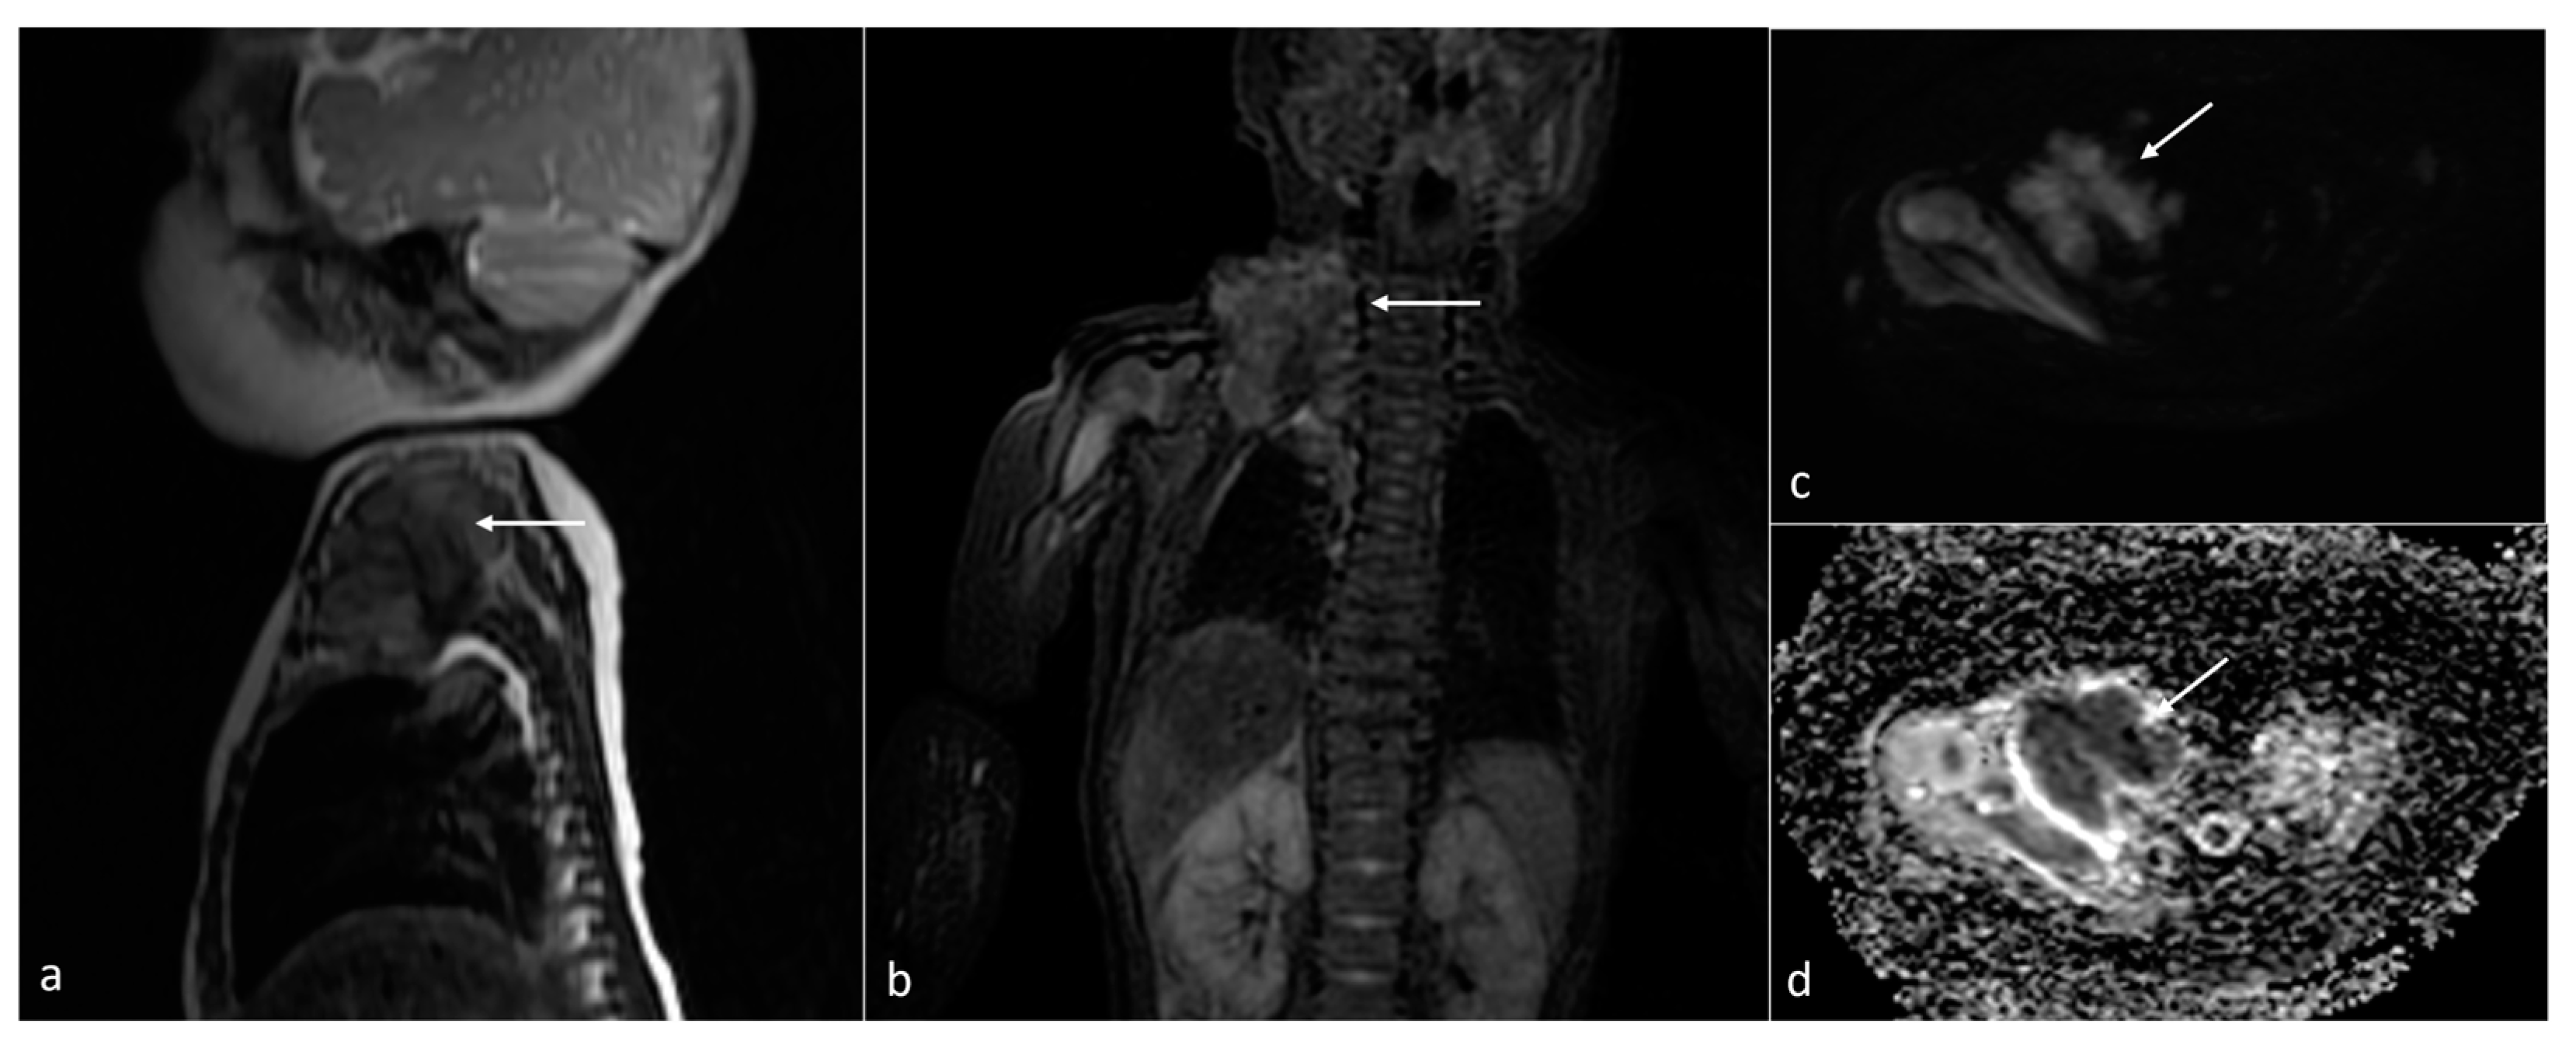

| Brain stem glioma | brain stem | 2 | [12.5–18.41] | no (1266–1430) | microcystic/solid | 1/2 | 0/1 |

| Desmoplastic infantile astrocytoma (DIA) | right middle cranial fossa | 1 | 52.7 | N/A | Solid | N/A | N/A |